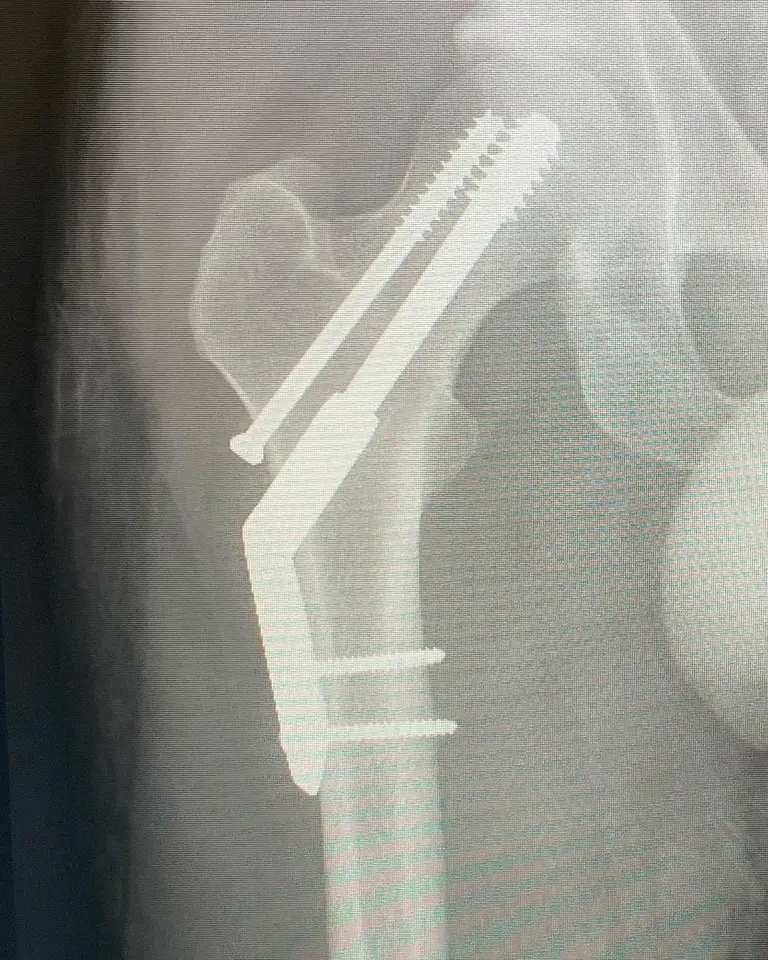

“Traté de correr media maratón, en lo que se convirtió en una fractura por estrés. Llegué a menos de 1km de la meta. Eso es la vida supongo” indicó el músico adjuntando una serie de registros de su pierna, incluyendo radiografías tras los procedimientos médicos.